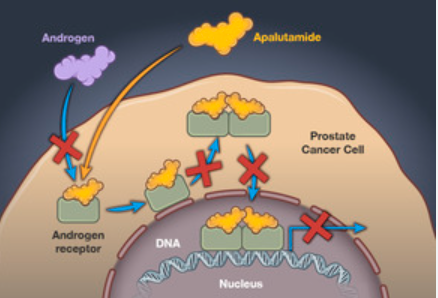

阿帕他胺作为一种新型AR抑制剂,抑制雄激素-AR结合的能力、阻止活化AR进入细胞核的能力、阻止AR与核内DNA结合的能力均强于传统AR抑制剂比卡鲁胺。在临床III期的关键研究TITAN中纳入了“All Comer”类型mHSPC人群,包括局限性前列腺癌复发转移患者、既往接受过全身/局部治疗的mHSPC患者、CHAARTED研究入组人群(高瘤负荷/低瘤负荷患者)以及LATITUDE研究入组人群(高危/低危mHSPC患者)等等,结果显示阿帕他胺具有显著的生存获益,并显示出快速、持久的PSA深度应答,且对于包括高危/高肿瘤负荷人群在内的所有类型患者均有显著获益[8],为mHSPC患者带来了高效且安全的治疗方案。